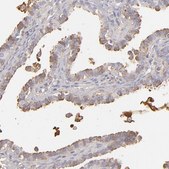

Anti-ABCC4 antibody produced in rabbit

immunohistochemistry: 1:200- 1:500

- IHC tissue array of 44 normal human tissues and 20 of the most common cancer type tissues.